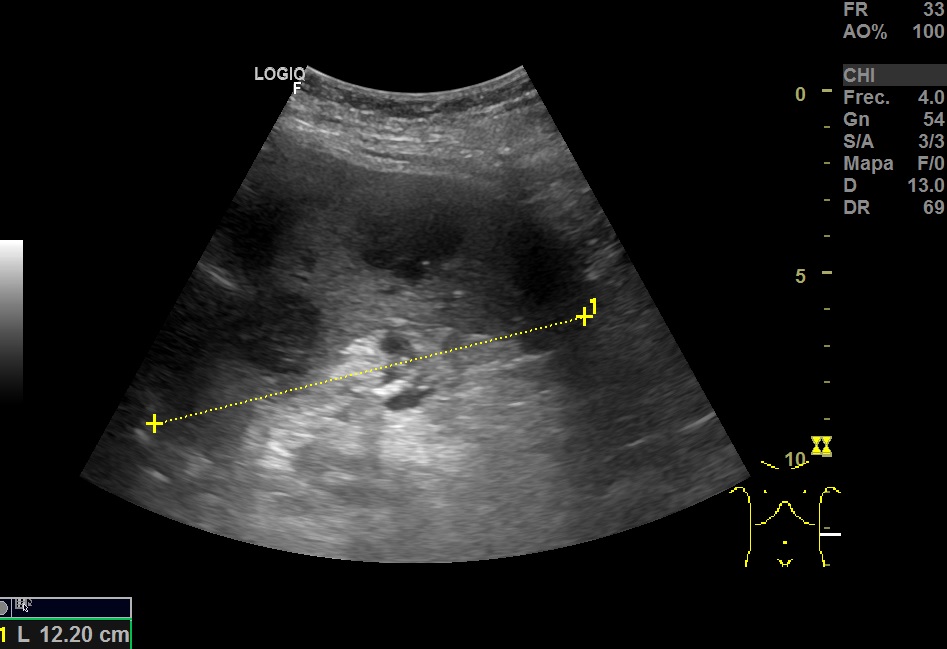

Hallazgos ecográfico: Esplenomegalia y varias lesiones focales hipoecogénicos de diferentes tamaños de bordes bien definidos en el bazo.

TAC abdominal: Bazo con múltiples imágenes hipodensas focales, mal delimitadas. Múltiples adenomegalias retrocrurales, mesentéricas, esplénicas y retroperitoneales.